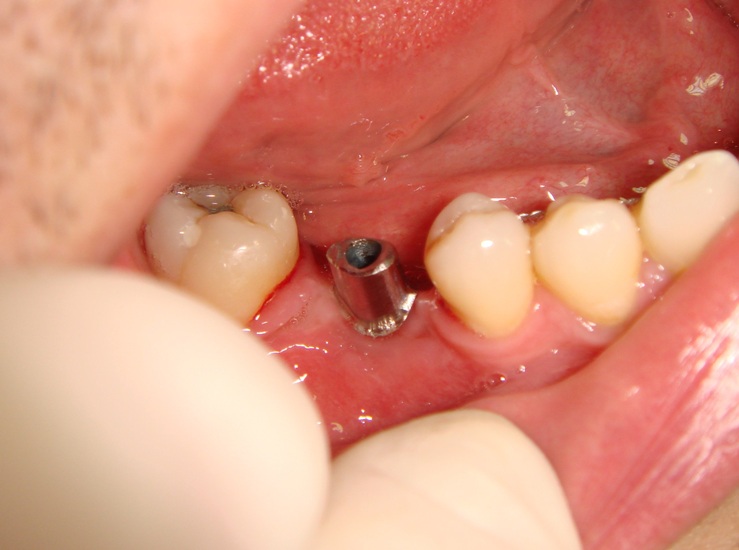

Photo 3. Oral cavity of the same patient: state of alveolar process, dentition and mucous membrane in the area of mandibular dentition defect at site of 46th tooth after implantation and formation of mucous membrane.